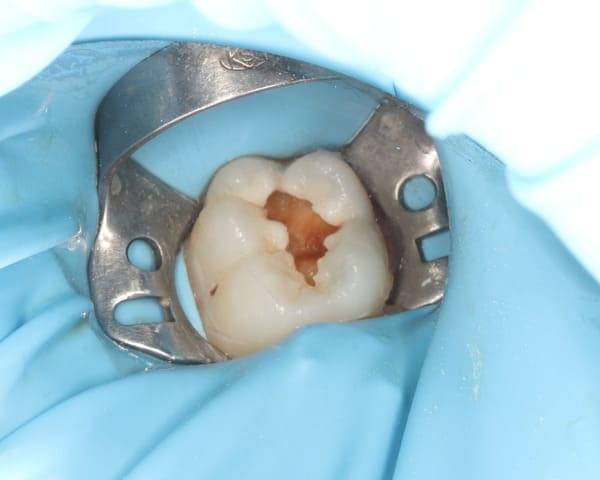

Робота з несформованими постійними зубами — найскладніша маніпуляція в дитячій стоматології. Ці зуби мають особливу будову, що ускладнює їх очищення та пломбування. У нашому Центрі Дитячої Стоматології в Києві ми володіємо передовими методиками, які дозволяють врятувати навіть найскладніші зуби.

Ця процедура вимагає скрупульозності та ювелірної точності. Наші лікарі працюють зі збільшенням (бінокулярами та мікроскопом), що дозволяє їм чітко бачити стан пульпи та ухвалювати правильні рішення.

Якщо ж пульпа не підлягає збереженню, ми використовуємо спеціалізовані методики та матеріали, які дозволяють закрити верхівки кореня перед пломбуванням. Це забезпечує надійний результат і запобігає ускладненням.